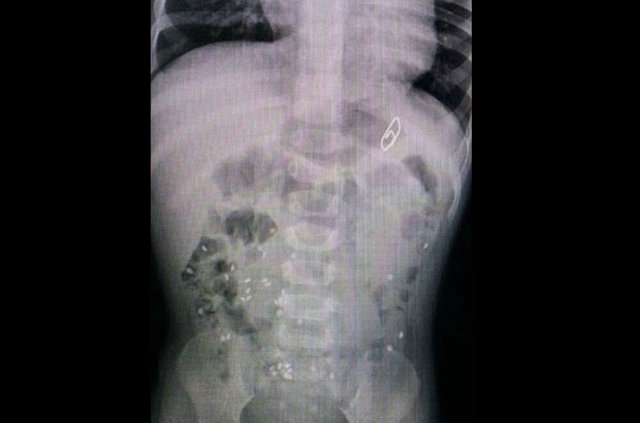

İzmir'deki Tepecik Eğitim ve Araştırma Hastanesi Çocuk Gastroenteroloji Bölümü'nün, yabancı cisim yutan çocukların nefes ve borusu ile midelerinden çıkarttığı, anahtarlık, madeni para, saat pili, ataç, çengelli iğne ve çivi gibi objeler görenleri şaşkına çevirdi.

Çocukların nefes ve borusu ile midelerinden çıkartılan, anahtarlık, madeni para, saat pili, ataç, çengelli iğne ve çivi gibi objeler görenleri şaşkına çevirdi. Anne ve babaların çok dikkatli olması gerektiğini söyleyen Doç. Dr. Maşallah Baran, şöyle dedi:

Genellikle yabancı cisimler 'X' ışınıyla görülebilir. Direk grafi ile metal ve 'X' ışınına duyarlı cisimleri rahatlıkla görebiliyoruz. Ama plastikleri göremiyoruz. Bu durumda oyuncağın bir parçasıyla yutulan parçayı anlamaya çalışıyoruz."

Aralarında iğne, metal kolye, vida, protez diş, dikiş iğnesi, kemik parçası, pisi pisi otu, çivi ve akasya dikeni de bulunan cisimleri koleksiyon yapan hekimler, vatandaşların ağızlarına aldıkları şeylere dikkat etmeleri gerektiğini dile getiriyor.